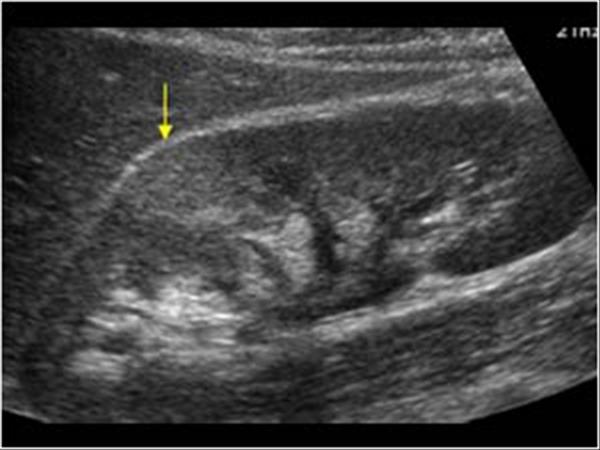

9. kép:

Vese gyulladás

A képen a nyíllal jelzett területnek megfelelően lehet látni egy elmosódott szélű világosabb területet, amely gyulladásra utal.